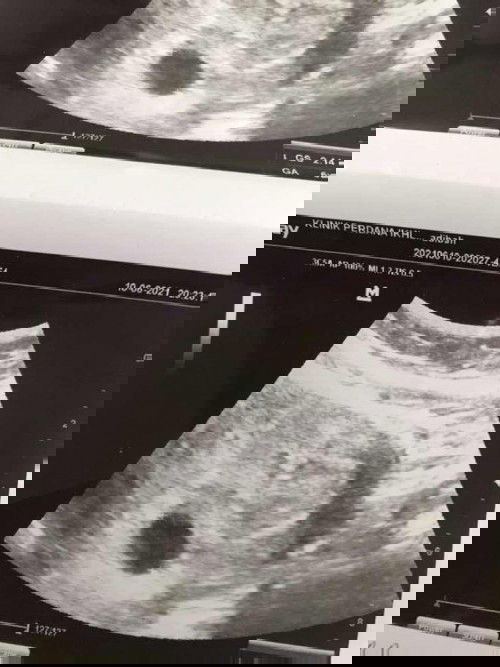

Sekarang kandungan dah 38minggu 3hari tapi takde tanda tanda nak bersalin last scan minggu lepas berat baby dah 3.4kg 😂 gdm on diet, Huhuhu nie nak bagi mama dia raya dulu ke tak nie 🤣 due 8/5 , 2/5 kena gi klinik ambik surat kalau tak bersalin jugak. Sesiapa ada tip tak bersalin sebelum serah diri 🤣 #firstmom #firstbaby #bantusharing #seriusnanya